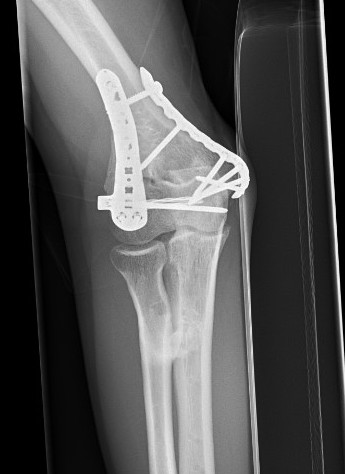

Elbow HOElbow HO Excision Post op

+/- hinged external fixator

Elbow Post HO Excision